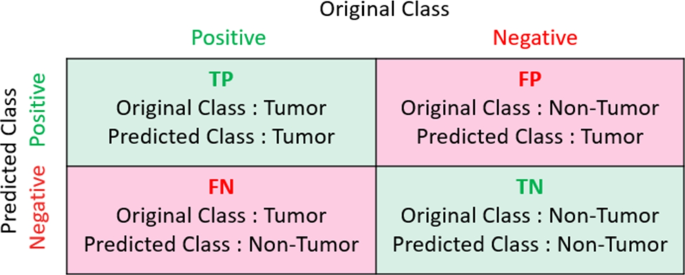

Sometimes the only way to make a definitive diagnosis of a brain tumor is through a biopsy. The neurosurgeon performs the biopsy and the pathologist makes the final diagnosis, determining whether the tumor appears benign or malignant, and grading it accordingly.